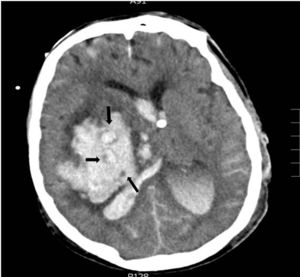

Con respecto a las variables radiológicas, tradicionalmente sabemos que la presencia de signos de hipertensión endocraneal en la TC es un indicador de gravedad, siendo el volumen de la lesión uno de los factores determinantes de mal pronóstico14,24; en el caso de las hemorragias, diversos estudios correlacionan el volumen del hematoma con la mortalidad a corto y largo plazo11,15,18,26-30 (tabla 3). La presencia de sangre intraventricular y su volumen, la localización infratentorial de la hemorragia, o la desviación de línea media, son también otros factores determinantes de mal pronóstico13,26,28,31,32. En pacientes con hemorragia intracerebral, la ausencia de reflejo corneal junto con el «signo del remolino» en la TC (fig. 2), que indica sangrado activo en el interior del hematoma, se han asociado a evolución de ME10 por una mayor probabilidad de expansión del hematoma, al igual que la presencia de spot sign en el angio-TC que también indica hemorragia activa33. En nuestra serie todos los pacientes fallecieron en situación de ME y presentaban signos de hipertensión endocraneal en la TC; los signos radiológicos que en nuestro estudio se asocian de forma significativa con una evolución a ME en las primeras 24 horas son el desplazamiento de línea media, la presencia de hidrocefalia activa, el borramiento completo de las cisternas basales, el borramiento de los surcos, la pérdida de diferenciación córtico-subcortical y la ausencia de cisterna supraselar.

Hemorragia en ganglios basales derechos con vertido ventricular y desplazamiento de línea media. En el interior del hematoma se observa el «signo del remolino», las flechas indican áreas con diferentes densidades; las pequeñas áreas hipodensas se corresponden con focos de sangrado activo por arteriolas y vénulas